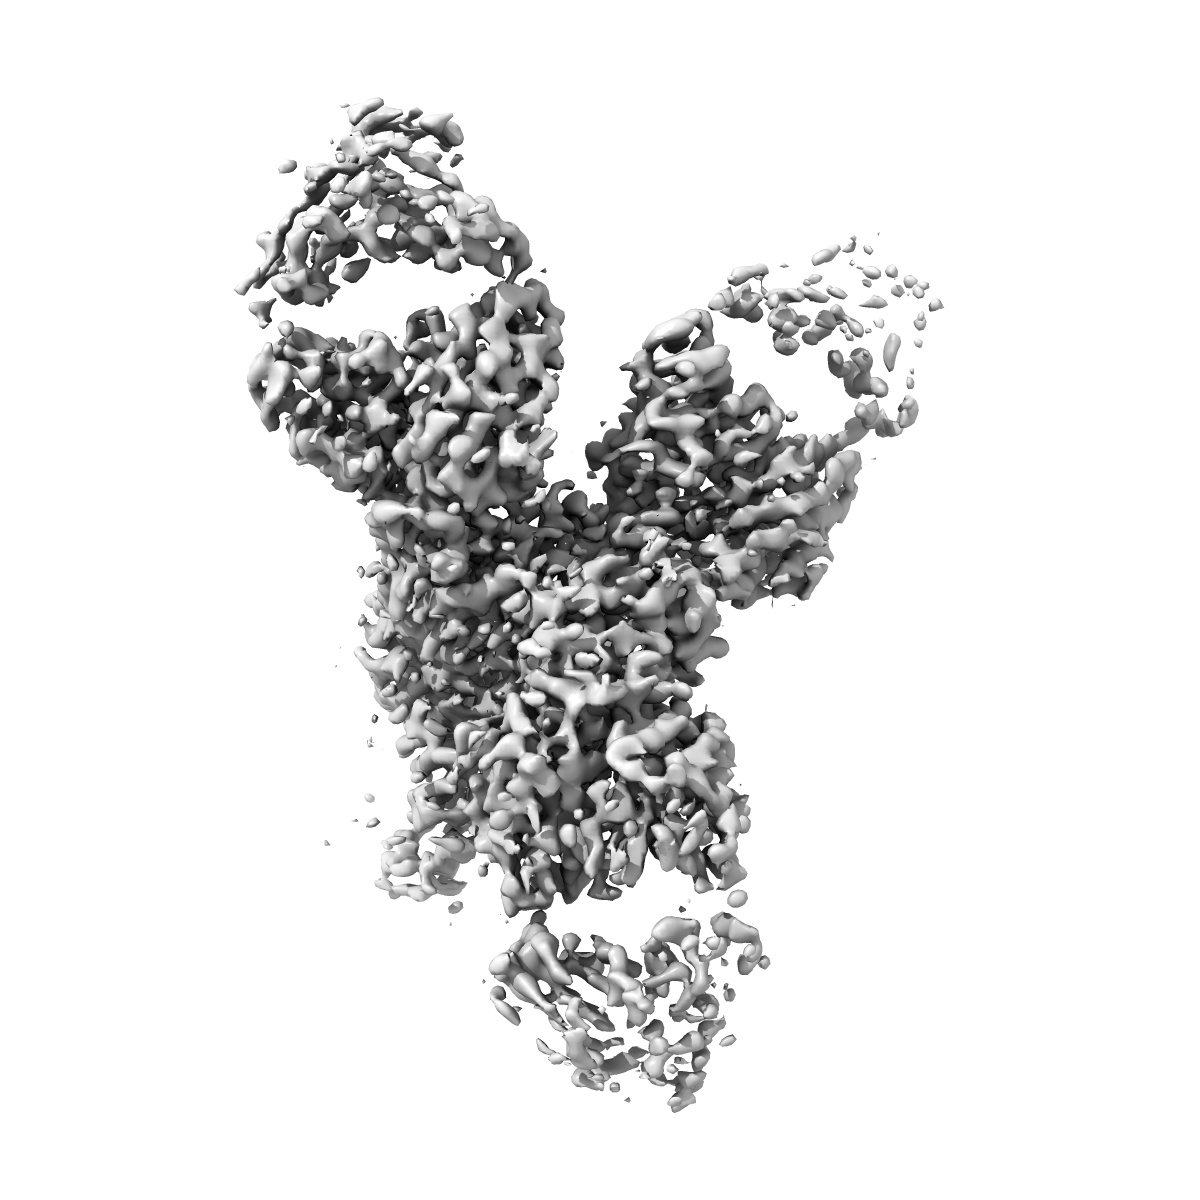

HEV ORF2 protein in complex with Fabs Es1.114 and Es5.127

Sample: Ternary complex of the HEV ORF2 protein with the Fab fragments of the monoclonal antibodies Es5.127 and Es1.114

Fitted models: 9fq3